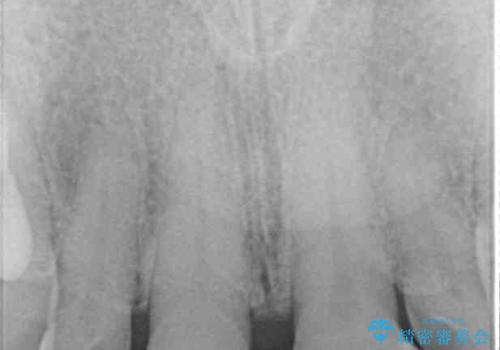

- 前歯の目立つ隙間を気にして来院された患者様です。

高校生の頃に矯正治療を行ったものの、強い咬合力により上顎が拡大され、正中に隙間ができてしまいました。

通常では歯の周囲全体を削った上でクラウンを装着することが多いのですが、咬合力が非常に強く、クラウンではセラミックが欠けてしまう可能性が考えられたため、咬合を変えることとのないラミネートベニアにて治療を行うこととしました。